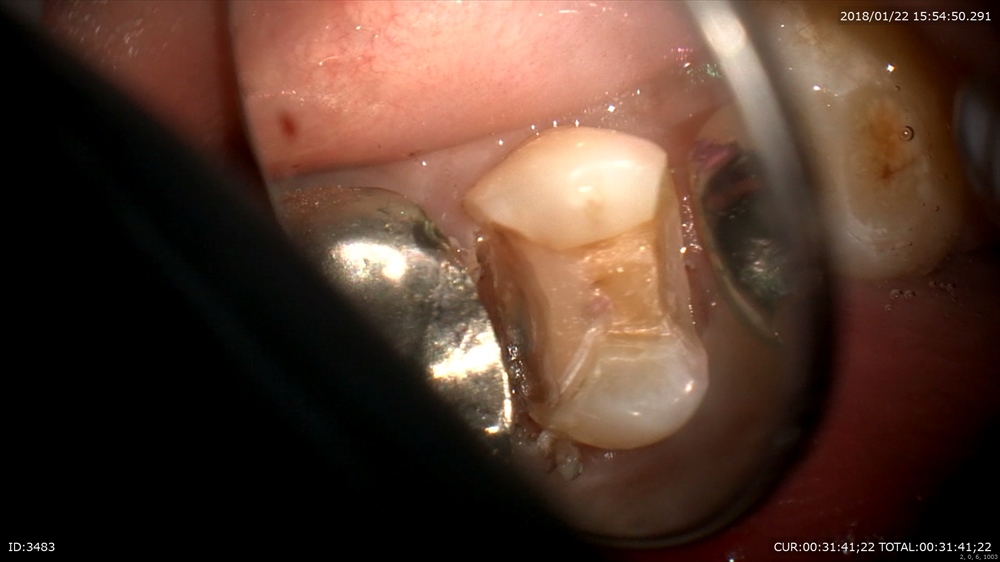

丁寧に。深い。歯茎の中まで。銀歯の恐ろしさ。。

ここで電気メス!(無痛)

こんな器具があると無痛で止血と形成が可能です。

コンポジットでビルドアップ

これで精密な型をとります。患者さまにもこの画像をしっかり説明!安心の治療。